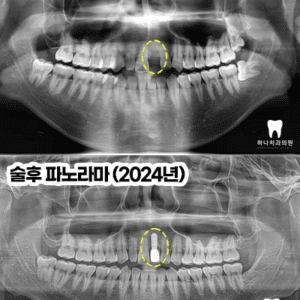

울산삼산동치과 매복된 사랑니 발치와 임플란트 수복(대합치 형태 회복)

울산삼산동치과 매복된 사랑니 발치와 임플란트 수복(대합치 형태 회복) 안녕하세요! 하나치과입니다~:) ​ 백세 시대라 불리는 요즘, 오복 중 하나로 여겼던 치아의 기능은 삶의 질을 좌우하는 요소가 될 수 있는데요. ​ 현대사회에 들어서면서 잘못된 식습관과 치아 건강 관리로 노령층의 전유물로만 여겼던 임플란트가 젊은 연령층에서도 증가하고 있습니다. ​ 치과 치료에 대한 두려움이나 시간, 더보기…